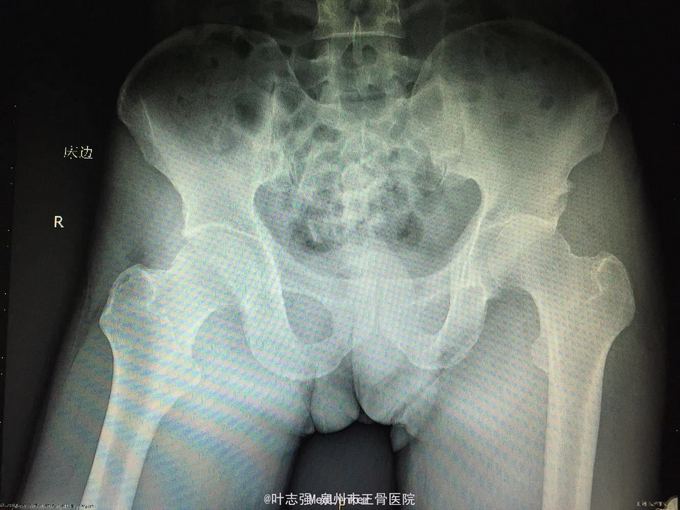

髋臼骨折伴髋关节后脱位ORIF

车祸致左髋部疼痛、活动受限1天。 53岁男性

左髋臼骨折伴髋关节后脱位 行生命支持,股骨髁上骨牵引,